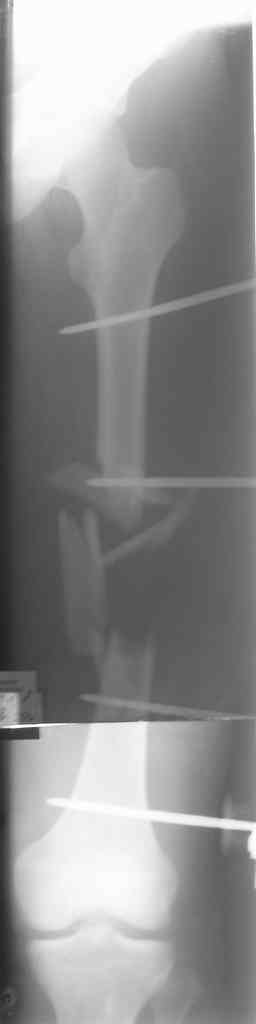

Вчера сделали снимки - положение отломков и осколков вот такое. На перевязке: из раны небольшое кол-во сгустков крови с примесью гноя , хотя бедро спокойное, гипертермии ни локальной ни общей нет. Вопрос: как быть дальше? открывать рану, "чистить" ее, наладить ее перфузию АС, АБ? что делать с осколками, попробовать перекрыть область перелома с фиксацией основных отломков аппаратом. Или осколки убрать и состыковать основные отломки с жутким укорочением и большими проблемами при зашивании раны?

Антон, а где Вы находитесь? Здесь все-таки оптимальнее после санации очага (обработка, лаваж, спейсер с антибиотиками) сделать закрытый

интрамедуллярный остеосинтез либо после спейсера, либо гвоздем с антибактериальным покрытием. Если такой вид помощи недоступен у вас, может быть, есть возможность пациента переправить в другой центр с

большими возможностями?

Свободные костные отломки, несвязанные с живыми мягкими тканями в условиях инфицированного перелома, необходимо удалить.